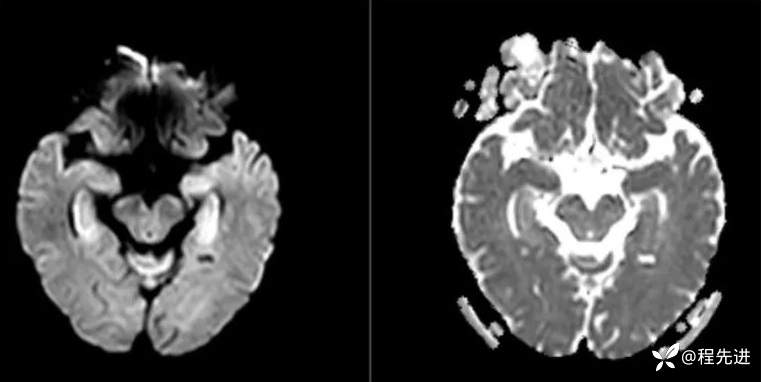

MRI平扫+增强:

DWI、ADC: